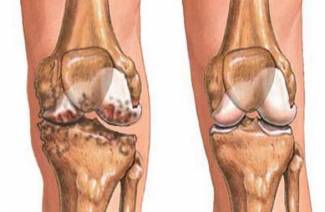

- osteocondrosis;

- En caso de daño a las articulaciones y al tejido conectivo, se requiere un curso de preparaciones regenerativas, terapia de ejercicios, electroforesis, y con una hernia intervertebral, se indica una operación para extirparla.